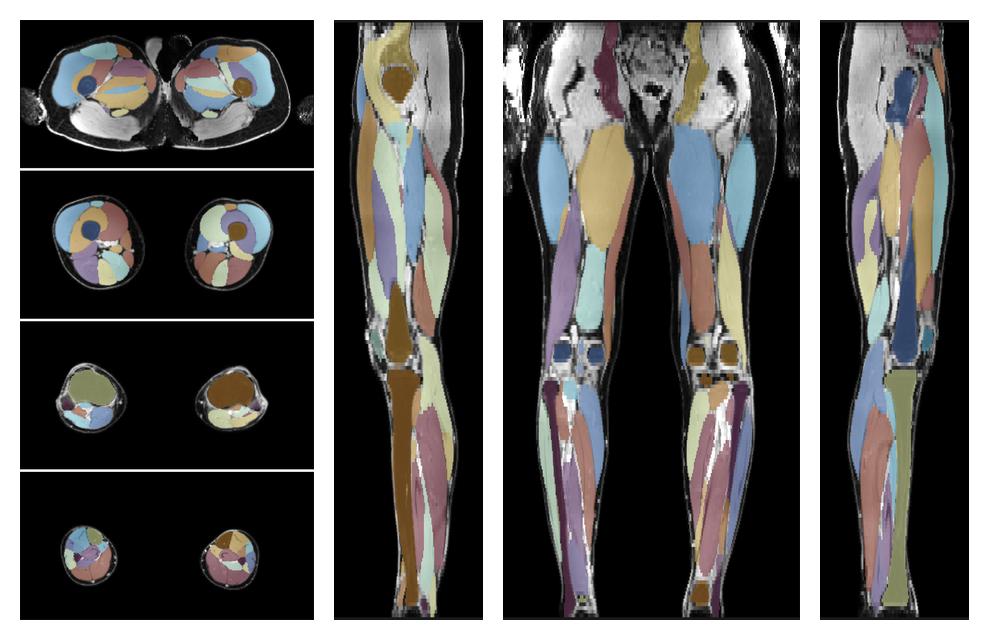

Muscle segmentation

Convolution neural network based (UNET) fiber automated muscle segmentation, for information look here».

• Automated muscle and bone segmentation.

Overlay of automated muscle segmentation labels on dixon water image.